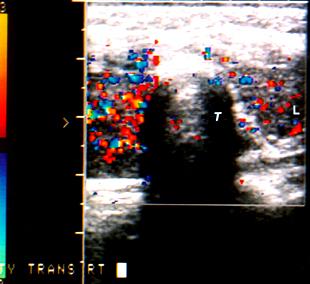

Ecografie tiroidiana : LD 6,1/3/2,6 cm, ecostructura hipoecogena, intens neomogena prin prezenta in 1/3 superioara a unui nodul de 2,1/1,8cm, hipoecogen, intens vascularizat si 1/3 inferioara a unui alt nodul de 1,3/1 cm, hipoecogen, vascularizat; restul lobului cu vascularizatie usor redusa.

Istm 0,4cm

LS 4,9/2/1,8 cm, hipoecogen, neomogen prin prezenta in 1/3 medie a 3 noduli hipoecogeni infracentimetrici, vascularizati si in 1/3 inferioara a unui nodul de 0,9/1,2 cm, hipoecogen, intens vascularizat ; restul lobului cu vascularizatie normala.

Fara adenopatii laterocervicale vizibile ecografic.